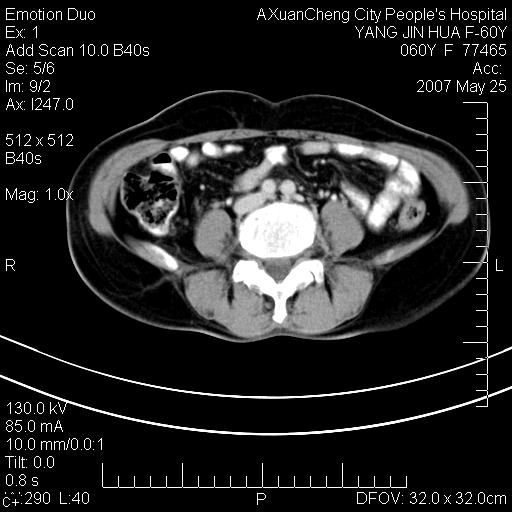

左背部皮下良性肿瘤,密度不均,边界不清,内有脂肪、钙化,增强扫描无明显强化,血管平滑肌脂肪瘤?进一步诊断有困难,建议穿刺活检。

左侧背部皮下混杂密度肿块,结构较疏松,边缘欠光整,内有多发斑点状钙化,考虑:皮下血管瘤。

左背部皮下良性肿瘤,密度不均,边界不清,内有脂肪、钙化,增强扫描无明显强化,血管平滑肌脂肪瘤?进一步诊断有困难,建议穿刺活检。还有,我想还是问一下病史,患者有外伤史吗?能否完全排除外伤后机化的....

其内可见斑点状静脉石,血管瘤有时就不增强化,还是血管瘤。

1、病灶内有小点状钙化,静脉石?这可是血管瘤诊断的重要征象

2、病灶内有脂肪组织增生,血管瘤有此特点

还是考虑皮下血管瘤,强化不明显可能跟大量血栓形成有关,好多战友考虑血管平滑肌脂肪瘤,血管平滑肌脂肪瘤的血管就不强化么?只要有血管就都应该强化。